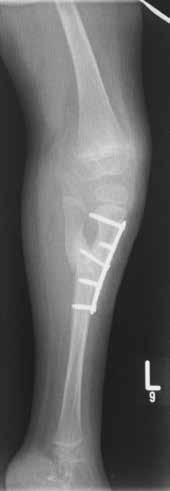

- Im Oktober 2009 erfolgt die Erstvorstellung im Universitätsklinikum Münster, im März 2010 die operative Distraktion, Redression und Rekonstruktion der Deformitäten mit externen Fixateuren (Abb. 5a). Die Fixateure werden über ein halbes Jahr in zwei Phasen à drei Monaten mit täglichem Redressment angepasst.

- Der rechte Fixateur distrahiert und fixiert Oberschenkel, Unterschenkel und Fuß. Linksseitig wird nur der Unterschenkel zum Fuß in Stellung gebracht.

- Im Oktober 2010 erfolgt eine operative Unterstellung mit Kirschnerdrähten am linken US und Fuß, am rechten OS und US und am rechten US und Fuß. Anschließend findet ein 10-wöchiges Gipsredressment statt.

- Im Mai 2013 wird der K‑Draht entfernt und eine Pseudarthroseanfrischung sowie eine Osteotomie der tibiofibularen Synostose durchgeführt.